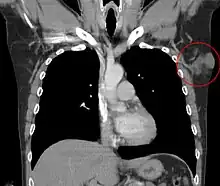

Dermatofibrosarcoma protuberans of the left axilla. CT, coronal reconstruction

Treatment is primarily surgical, with chemotherapy and radiation therapy used if clear resection margins are not acquired.[26]